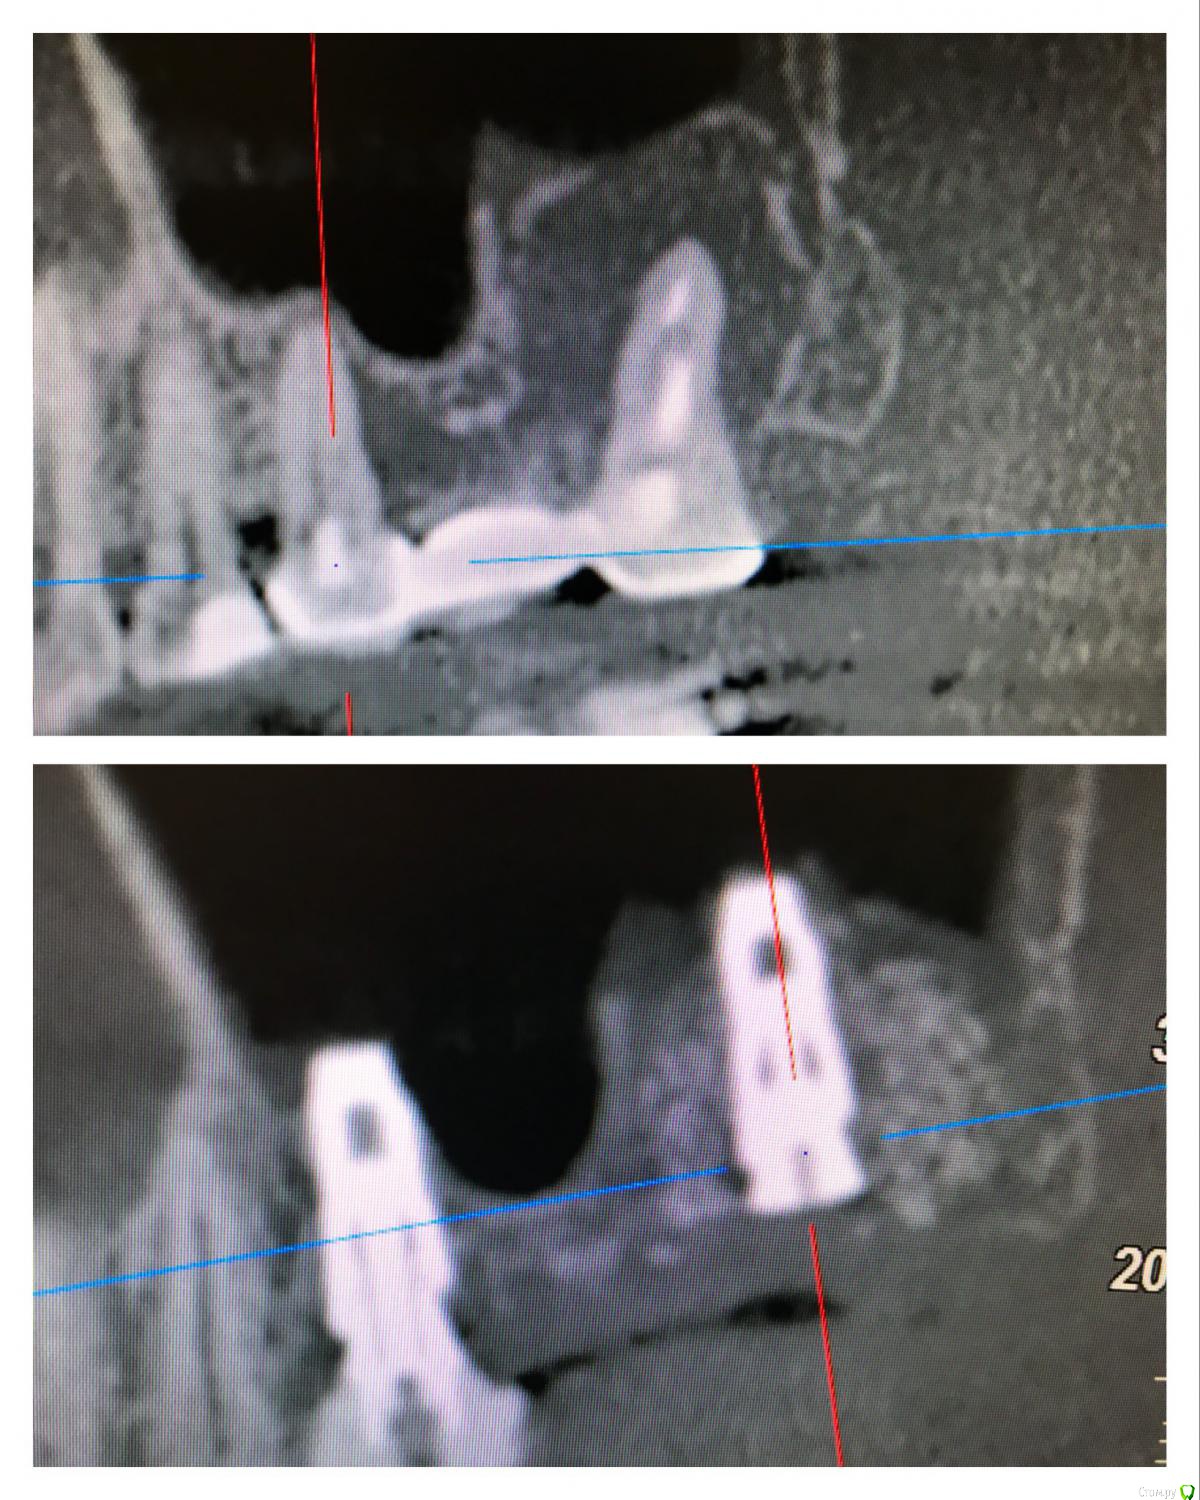

vse32 Опубликовано 6 ноября, 2019 Поделиться Опубликовано 6 ноября, 2019 Я стоматолог терапевт, поэтому вопрос почти как от обывателя.16 зуб, женщина около 35 лет (не видела ее, коллега мужа по работе). В сторонней клинике сделали ОПТГ и КТ и рекомендовали удаление с одномоментной имплантацией. Со слов женщины предложен корейский имплантат за х рублей + подсадка за х рублей. Или американский имплантат за 2х рублей без подсадок.Вопрос - нормально ли это делать одномоментно при наличии кистогранулемы (вне обострения).Лечить эндодонтически могу, но сомневаюсь в гарантийности работы. Ссылка на комментарий

колесников Опубликовано 7 ноября, 2019 Поделиться Опубликовано 7 ноября, 2019 (изменено) всё возможно в этой жизни. Интересно посмотреть такой кейс. Но это смущает а что Вас смущает? Ситуация очень благоприятная,киста сама сделала синуслифтинг,если сделаем паузу-потеряем этот объём Изменено 7 ноября, 2019 пользователем колесников 4 Ссылка на комментарий

Evikrol Опубликовано 10 ноября, 2019 Поделиться Опубликовано 10 ноября, 2019 а что Вас смущает? Ситуация очень благоприятная,киста сама сделала синуслифтинг,если сделаем паузу-потеряем этот объёмКакой протокол имплантации в таком случае, как быть уверенным что инфекции не осталось в полости с гноем? Как вообще правильно? Удалить, обильно промыть эндошприцем, крутить с графтом или без? Кюретажить или нет? Ссылка на комментарий

колесников Опубликовано 10 ноября, 2019 Поделиться Опубликовано 10 ноября, 2019 Какой протокол имплантации в таком случае, как быть уверенным что инфекции не осталось в полости с гноем? Как вообще правильно? Удалить, обильно промыть эндошприцем, крутить с графтом или без? Кюретажить или нет? ну ладно пациенты,но Вы то! Какой гной! Где? Вылущили оболочку-все чисто. Обычно и вылущивать ничего не нужно,вынули зуб ,а на нем висит оболочка. Ревизию по стенкам конечно лучше делать и промыть. Грануляции от жидкости набухают и визуализируются. Лунка под капсулой стерильна. Главное чтобы слюна не попала и не остались грануляции. Я всегда использую графт,тк такой объём сгусток не в состоянии сохранить,распадётся. 1 Ссылка на комментарий

rimtar Опубликовано 11 ноября, 2019 Поделиться Опубликовано 11 ноября, 2019 а что Вас смущает? Ситуация очень благоприятная,киста сама сделала синуслифтинг,если сделаем паузу-потеряем этот объёмкрасивая идея и фото, но как фиксирован имплант? просто лежит в графте? 1 Ссылка на комментарий

Irouil Опубликовано 11 ноября, 2019 Поделиться Опубликовано 11 ноября, 2019 (изменено) красивая идея и фото, но как фиксирован имплант? просто лежит в графте?Бикортикально (вернее - в кортикалке дна пазухи) и в перегородке, там где она осталась. Если широкий винт - в стенках лунки. В таких рейсах и 10 Н*см достаточно Изменено 11 ноября, 2019 пользователем Irouil 1 Ссылка на комментарий

колесников Опубликовано 11 ноября, 2019 Поделиться Опубликовано 11 ноября, 2019 (изменено) Просто лежать в графте на в/ч он не может,силу тяжести никто не отменял. Имплант обязательно должен контактировать с нативной костью и иметь хоть минимальную ,но стабильность. Стабильность,как ответили выше ,можно получить зацепившись апексом за свод, где то за перегородку,и фдм иногда помогает. Были случаи стабильности только от супраструктуры и имплант интегрировался.Это не просто идея и красивое фото,это вполне себе рабочая модель Изменено 11 ноября, 2019 пользователем колесников 4 Ссылка на комментарий